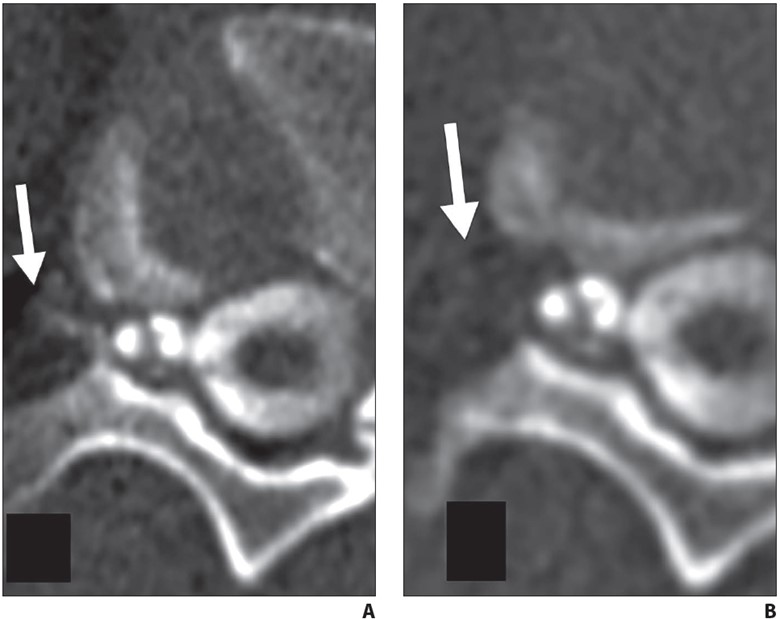

Fig. 7—45-year-old man with orthostatic headaches and confirmed ventral dural defect at T1-2 level.

A and B, Sequential axial CT slices obtained during epidural blood patching show far lateral transmuscular approach using 15-cm spinal needle (arrow) to reach ventral epidural space at T1-2 level.